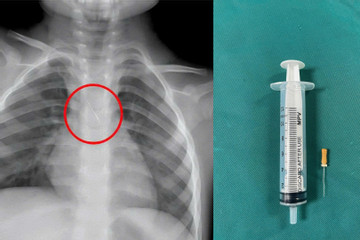

Bé 3 tuổi ở Quảng Trị bị kim chọc tủy kẹt trong đường thở

Trong lúc làm răng, bé 3 tuổi không may bị sặc kim chọc tủy vào đường thở. Trong tình huống vừa nguy hiểm vừa khó, các bác sĩ đã khẩn trương gắp thành công dị vật cho bện...